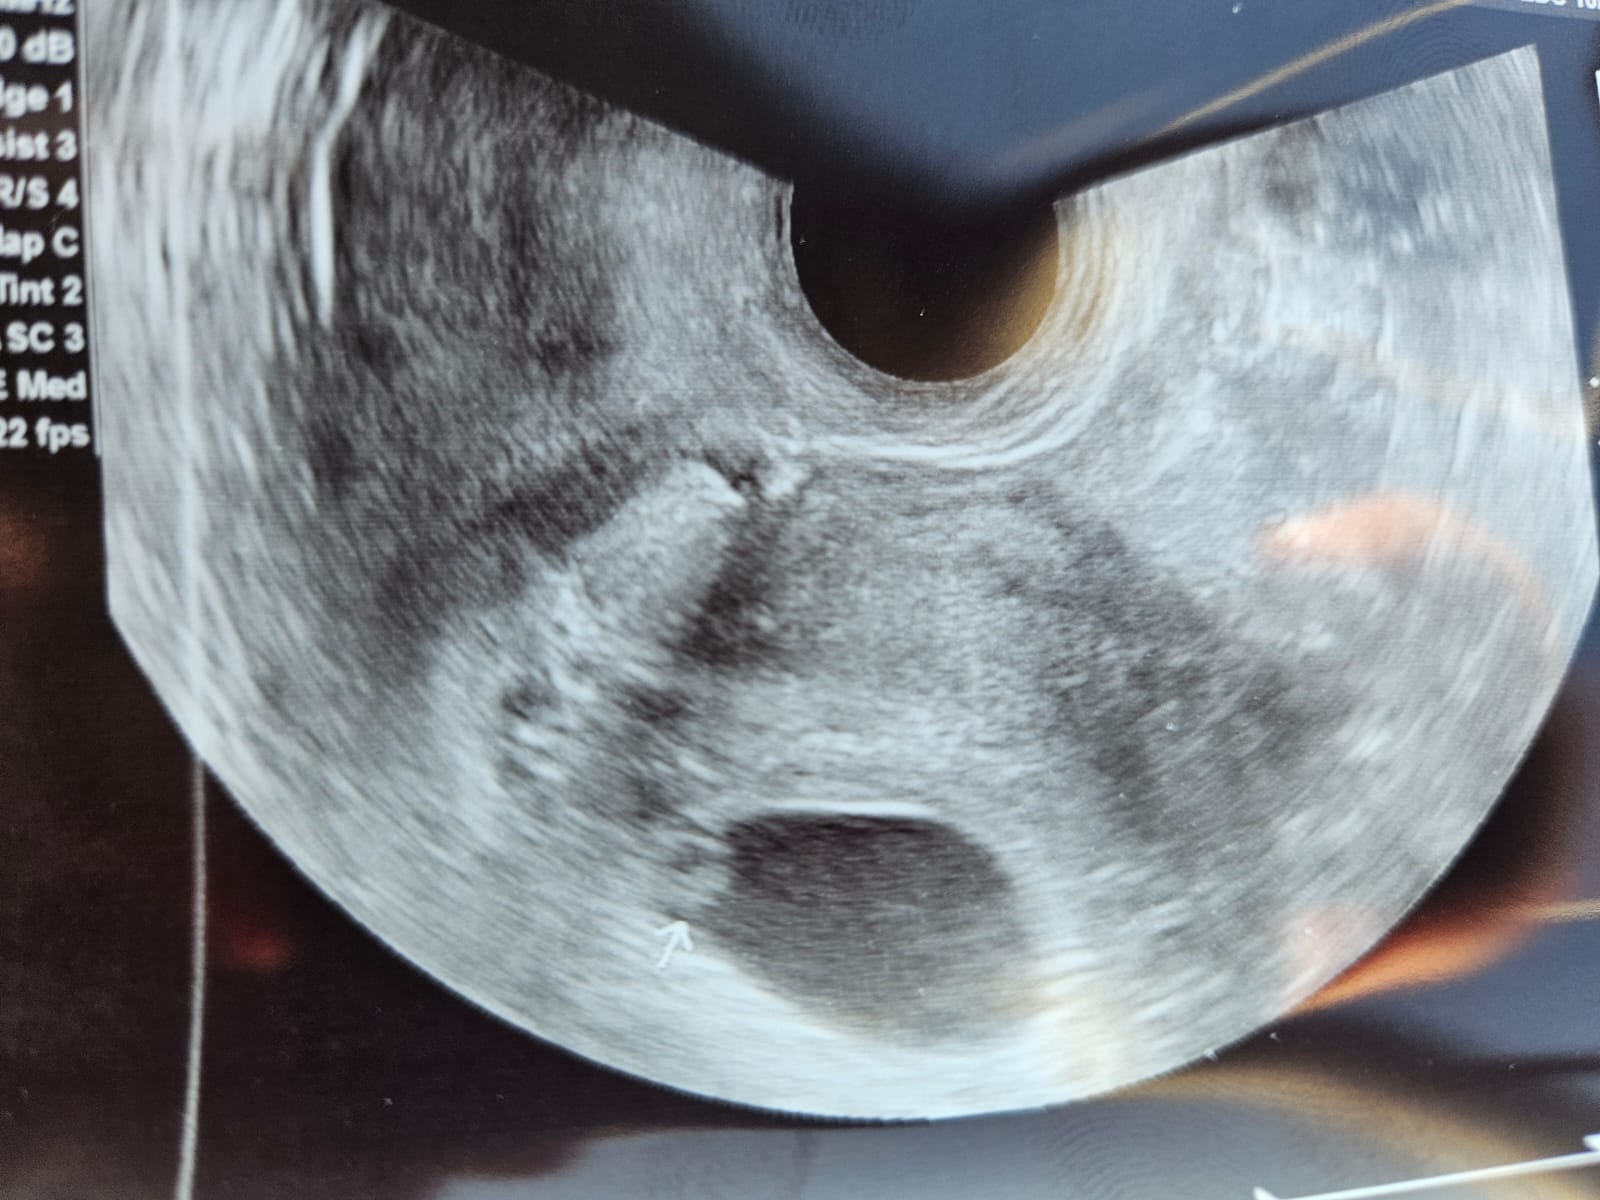

Tu mam zdjęcie z wtorku (7+4)